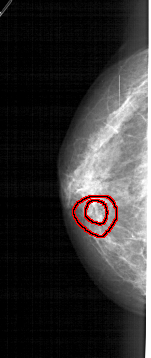

FILE: A_1938_1.LEFT_MLO.OVERLAY

TOTAL_ABNORMALITIES 1

ABNORMALITY 1

LESION_TYPE MASS SHAPE IRREGULAR MARGINS SPICULATED

ASSESSMENT 5

SUBTLETY 2

PATHOLOGY BENIGN

TOTAL_OUTLINES 2